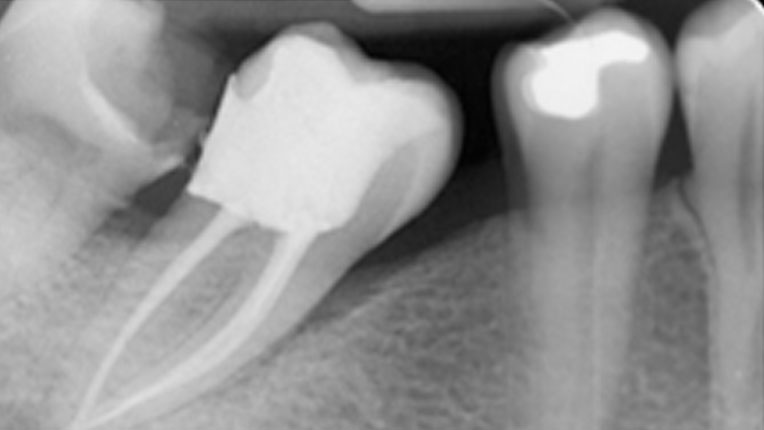

La Endodoncia es el procedimiento que se realiza para conservar el diente , que de otra manera tendría que ser extraido.

Disponemos del mejor Equipo en cuanto a personal y tecnología, ultimas tecnicas en Tratamientos sin dolor. Equipo de Endodoncia de Ultima Generación , sistema rotatorio con localizador integrado y Endodoncistas extensamente formados.

La mayoria de las Endodoncias se realizan en una sesion , es decir en una cita , existen determinados casos , por ejemplo cuando la infección es muy grande que es recomendable hacerlo en dos sesiones.